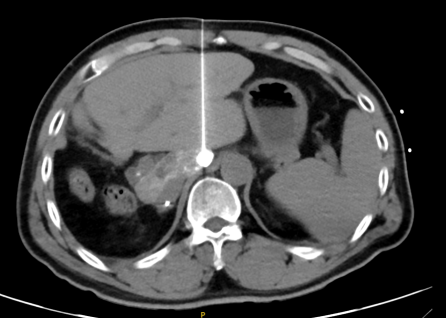

动脉化疗栓塞术,该手术在局麻下仅在大腿根部通过米粒大小的伤口,经动脉进入介入导管,并通过DSA直视下将导管精准选择至肝脏肿瘤供血血管,通过导管局部灌注化疗药物及碘化油栓塞药物,达到精准****的效果。

图片

介入术中显示的肿瘤血管及肿瘤病灶